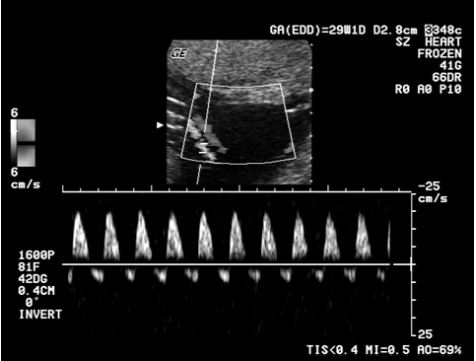

33 承上題,真真接受了全血球計數及一般生化檢查,白血球 11.2 K/µL,血小板 67 K/µL,血紅素 10.3 g/dL, AST 160 U/L,ALT 180 U/L,LDH 950 U/L;休息後重測一次血壓為 160/110 mmHg,且頭痛欲裂, 進一步超音波臍帶動脈都卜勒檢查發現如下。下列敘述何者錯誤?

(A)真真的情形符合 HELLP 症候群 (B)真真的胎兒有嚴重胎內成長遲滯的情形(fetal growth restriction) (C)真真的血液中 soluble Fms-like tyrosine kinase 1(sFlt1)及 placental growth factor(PLGF)的數量 與生物可利用性(bioavailability)皆較一般孕婦為高 (D)真真的情形已符合嚴重子癎前症(severe preeclampsia),需要立刻進一步處置